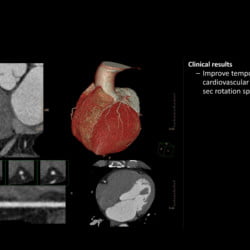

Incisive CT de 64 canais e 128 cortes

Especificações Técnicas do Tomógrafo Philips Incisive CT

| Tipo de tubo | Tubo vMRC Cerâmico |

| Capacidade do tubo | 8 MHU |

| Configuração de kVp | 70, 80, 100, 120, 140 kV |

| Tamanho do bore | 72 cm |

| Cortes | até 128 cortes |

| Cobertura | 40 mm |

| Potência do gerador | 80 kW |

| Velocidade de rotação | até 0,35 s |